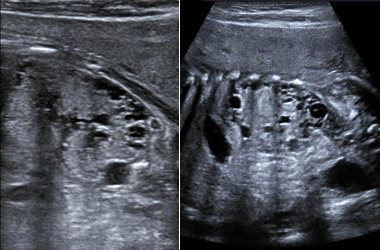

Common Ultrasound Procedures

UCSF’s ultrasound subspecialty provides the Bay Area’s most advanced and multidisciplinary ultrasound services. We offer, for example, the integrated services available for fetal therapy and UCSF’s outstanding ultrasound disease diagnosis, and the highest levels of real-time ultrasound imaging accuracy for transplant surgery.